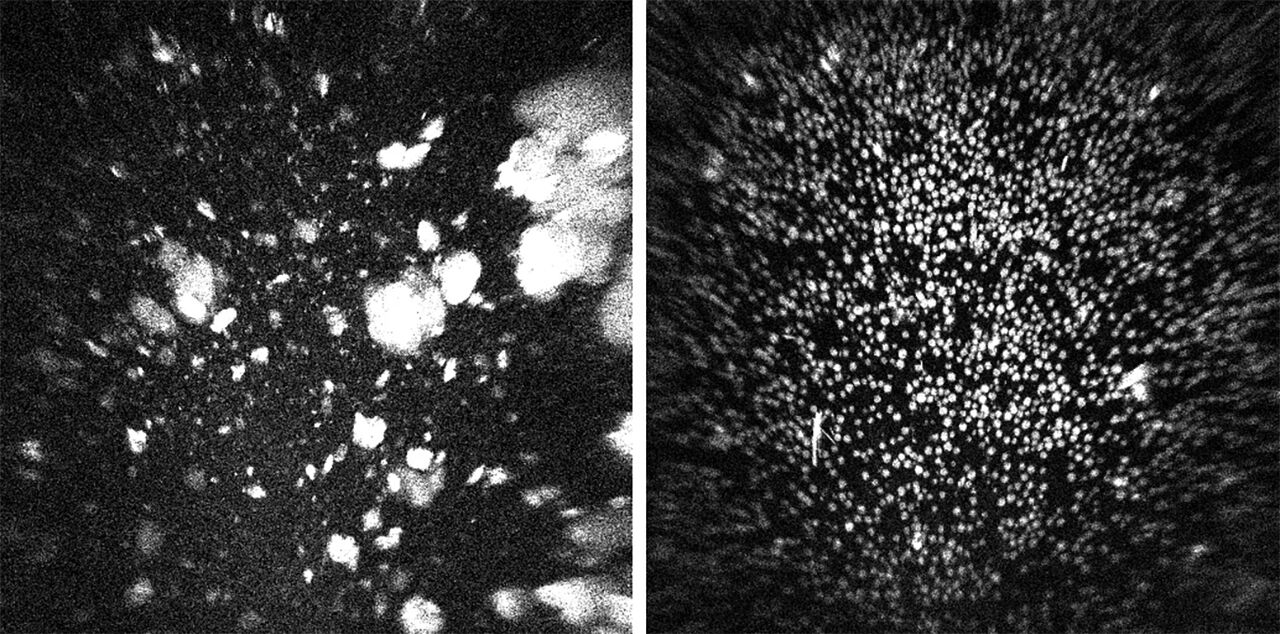

과거에 비해 발사 비용이 줄었다지만 여전히 비싼 비용과 각종 위험을 감수하고 우주로 가야 하는 이유는 바로 '미세중력'에 있습니다. 바이오 의약품의 주성분인 단백질을 지상에서 만들 때는 중력으로 인한 침전, 대류 현상을 피할 수 없습니다. 분자들이 바닥에 가라앉고 서로 엉겨 붙기도 해서, 결정이 울퉁불퉁하고 크기도 들쑥날쑥합니다. 불순물이 끼어들기도 쉽습니다. 반면 우주 공간의 미세중력 상태에서 침전, 대류 현상 없이 천천히 자라난 결정은 크기가 균일하며 순도가 높습니다. 순도 높은 단백질 결정은 매우 복잡한 단백질의 구조에 대한 이해를 돕고, 효과적인 신약을 개발하는 데 결정적인 도움을 줍니다. 고농도면서 점도는 낮은 단백질로의 변화, 즉 키트루다 제형 변화도 바로 여기서 시작된 것입니다.

▲ 지상 제조 단백질 결정(좌) - 우주 제조 단백질 결정(우) (출처=다국적 제약사 머크)